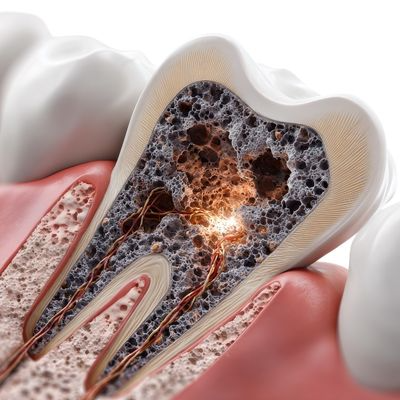

Çürük diş tedavisi, diş minesinde başlayan ve zaman içerisinde dentin tabakasına ilerleyen çürüklerin temizlenmesi işlemidir. Bu işlem dişin yeniden sağlıklı yapısına kavuşturulmasını amaçlar. Diş çürüğünün oluşma nedeni genellikle bakteri plağı, şekerli gıdalar ve yetersiz ağız hijyeni gibi faktörlerden kaynaklanır. Tedavi sürecinde öncelikli olarak çürük dokular temizlenir. Ardından dişin kaybettiği yapı dolgu materyalleri ile restore edilir. Bu işlem dişin fonksiyonunu korurken ileride oluşabilecek daha ciddi diş problemlerinin de önüne geçer.

Çürük diş tedavisi, çürüğün ilerleme seviyesine göre farklı yöntemlerle uygulanabilir. Çürüğün erken aşamada tespit edildiği durumlarda basit dolgu işlemleri yeterli olur. Ancak daha derin çürüklerde kanal tedavisi gibi daha kapsamlı işlemler gerekli olabilir. Düzenli diş kontrolleri çürüklerin erken dönemde fark edilmesini sağlar. Böylece tedavi daha kolay ve hızlı bir şekilde yapılabilir. Doğru fırçalama alışkanlıkları, diş ipi kullanımı ve dengeli beslenme gibi günlük bakım rutinleri de çürük oluşumunu büyük ölçüde önlemeye yardımcıdır.

Ön dişlerde görülen çürükler çoğunlukla plak birikimi, yetersiz ağız bakım uygulamaları veya sık tüketilen şekerli gıdalar nedeniyle ortaya çıkar. Çürük ilerlediğinde ise diş minesini aşar ve dentin tabakasına ulaşır. Sonrasında hassasiyet, renk değişimi veya küçük oyuklar şeklinde kendini gösterir. Bazı durumlarda dişin görünen kısmında görülen çürükler bazı zamanlarda da diş aralarında da gelişebilir. Özellikle diş yüzeyine yakın bölgelerde başlayan çürükler zaman içerisinde büyür ve daha geniş bir alanı etkiler.

Diş çürükleri erken dönemde fark edilip tedavi edildiğinde dişin doğal yapısının korunması mümkün olur. Bu doğrultuda diş çürüğü nasıl tedavi edilir sorusu merak edilen bir konudur. Çürük oluşumunda tedavi süreci diş hekimi tarafından yapılan detaylı bir muayene ile başlar. Diş yüzeylerinin incelenmesiyle başlayan süreçte gerekli görülen durumlarda röntgen görüntülerinden yararlanılır. Böylece çürüğün derinliği ve yayılımı değerlendirilir. Bu aşamada çürük tedavisi için uygulanacak yöntemin belirlenmesi oldukça önemlidir.

Tedavi sürecinde diş hekimi çürüğü oluşturan hasarlı dokuyu özel aletler yardımıyla temizler ve dişteki boşluk uygun dolgu materyalleri ile doldurulur. Böylece hem dişin yapısı hem de fonksiyonu korunur. Günümüzde estetik dolgu materyalleri diş rengine yakın tonlardadır. Bu özelliği ile görünür bölgelerde oldukça doğal bir sonuç sağlar. Çürüğün daha derin tabakalara ilerlediği ve sinir dokusuna yaklaştığı durumlarda kanal tedavisi gibi daha kapsamlı tedaviler gerekli olabilir. Bu tür durumlarda amaç, dişi çekmeden mümkün olduğunca ağız içinde sağlıklı şekilde kalmasını sağlamaktır.